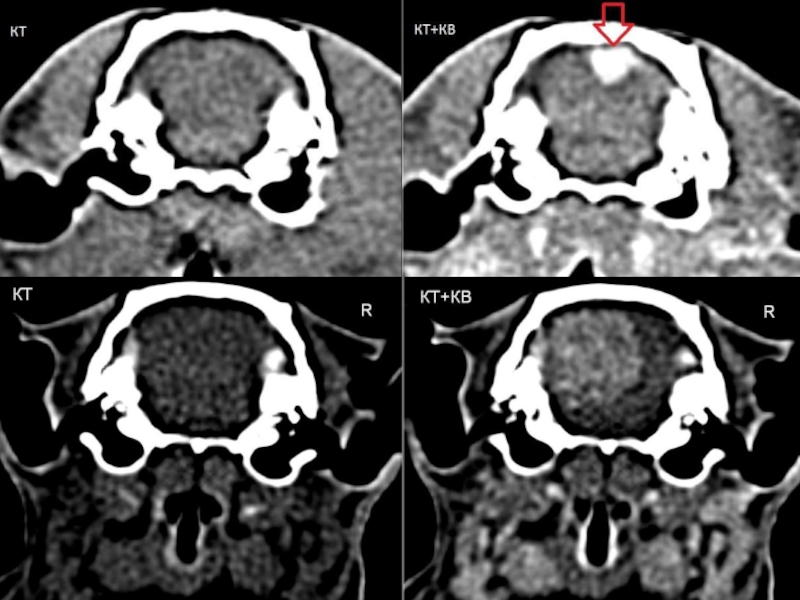

Компьютерная томография в неврологии презентация - 86 фото